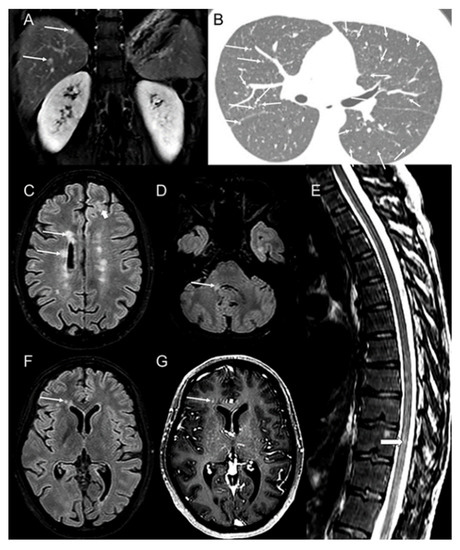

2. Case Illustration